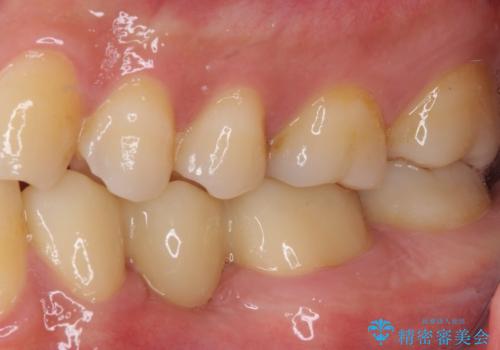

オールセラミックブリッジとしたことで、審美的かつ外れにくい補綴治療を行うことができました。